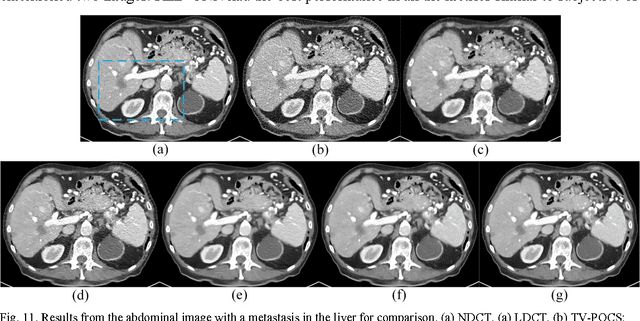

Given the potential X-ray radiation risk to the patient, low-dose CT has attracted a considerable interest in the medical imaging field. The current main stream low-dose CT methods include vendor-specific sinogram domain filtration and iterative reconstruction, but they need to access original raw data whose formats are not transparent to most users. Due to the difficulty of modeling the statistical characteristics in the image domain, the existing methods for directly processing reconstructed images cannot eliminate image noise very well while keeping structural details. Inspired by the idea of deep learning, here we combine the autoencoder, the deconvolution network, and shortcut connections into the residual encoder-decoder convolutional neural network (RED-CNN) for low-dose CT imaging. After patch-based training, the proposed RED-CNN achieves a competitive performance relative to the-state-of-art methods in both simulated and clinical cases. Especially, our method has been favorably evaluated in terms of noise suppression, structural preservation and lesion detection.